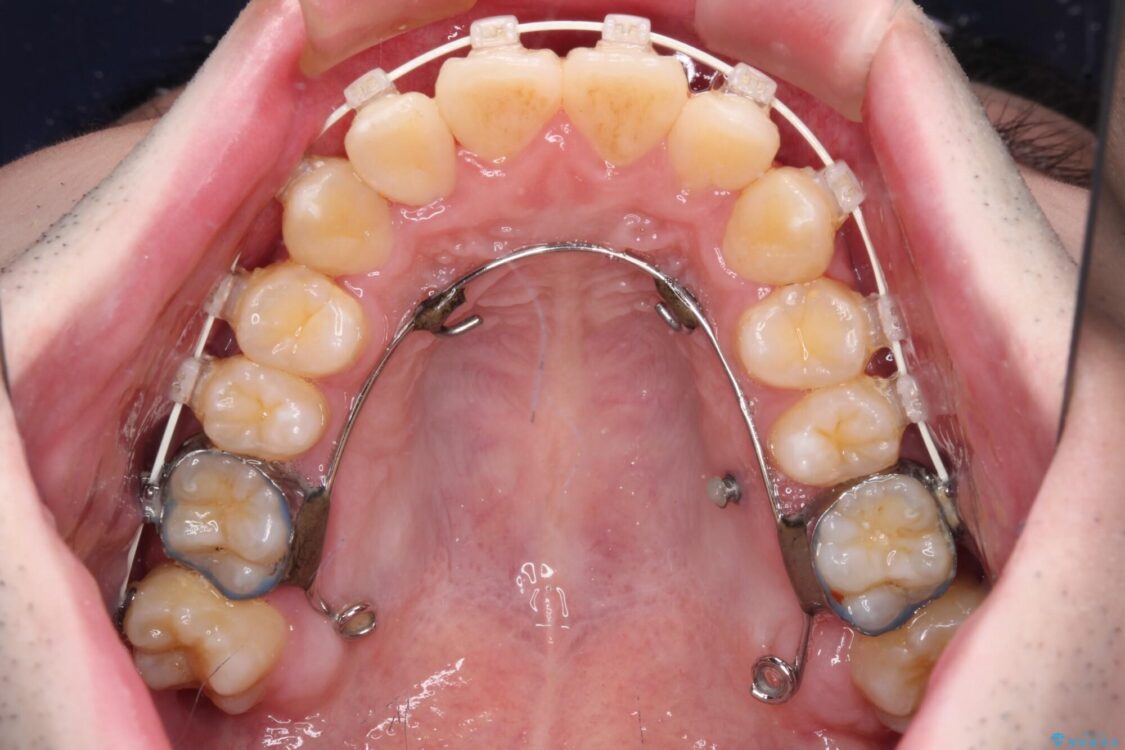

八重歯や奥歯の噛みにくさを気にして来院された患者様です。

前歯のクロスバイトや八重歯の他に、左右最後臼歯のシザーズバイト(鋏状咬合)が認められました。

シザーズバイト改善のために補助装置を使用しながら、ワイヤー装置にて全体の歯列を整えることとしました。

治療途中

• 全顎的なクロスバイト 補助装置を用いてワイヤー矯正 治療途中画像